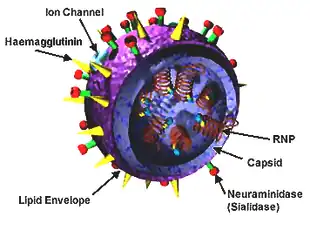

Influenzaviruses A, B, C, and D are very similar in overall structure.[8][56][57] The virus particle (also called the virion) is 80–120 nanometers in diameter such that the smallest virions adopt an elliptical shape.[58] The length of each particle varies considerably, owing to the fact that influenza is pleomorphic, and can be in excess of many tens of micrometers, producing filamentous virions.[59] However, despite these varied shapes, the viral particles of all influenza viruses are similar in composition.[60] These are made of a viral envelope containing the glycoproteins hemagglutinin and neuraminidase wrapped around a central core. The central core contains the viral RNA genome and other viral proteins that package and protect this RNA. RNA tends to be single stranded but in special cases it is double.[61] Unusually for a virus, its genome is not a single piece of nucleic acid; instead, it contains seven or eight pieces of segmented negative-sense RNA, each piece of RNA containing either one or two genes, which code for a gene product (protein).[60] For example, the influenza A genome contains 11 genes on eight pieces of RNA, encoding for 11 proteins: hemagglutinin (HA), neuraminidase (NA), nucleoprotein (NP), M1 (matrix 1 protein), M2, NS1 (non-structural protein 1), NS2 (other name is NEP, nuclear export protein), PA, PB1 (polymerase basic 1), PB1-F2 and PB2.[62]

Hemagglutinin (HA) and neuraminidase (NA) are the two large glycoproteins on the outside of the viral particles. HA is a lectin that mediates binding of the virus to target cells and entry of the viral genome into the target cell, while NA is involved in the release of progeny virus from infected cells, by cleaving sugars that bind the mature viral particles.[63] Thus, these proteins are targets for antiviral medications.[64] Furthermore, they are antigens to which antibodies can be raised. Influenza A viruses are classified into subtypes based on antibody responses to HA and NA. These different types of HA and NA form the basis of the H and N distinctions in, for example, H5N1.[65] There are 18 H and 11 N subtypes known, but only H 1, 2 and 3, and N 1 and 2 are commonly found in humans.[66][67]